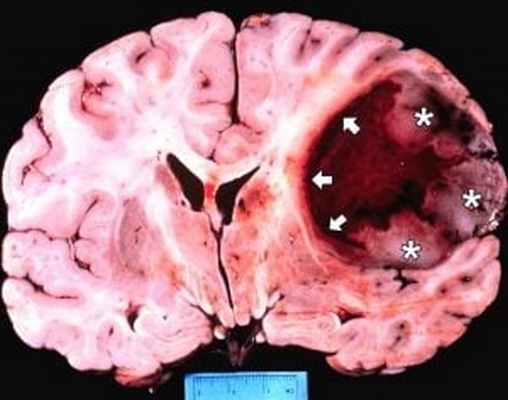

Обычно на момент установки диагноза ГБМ является крупной опухолью. Часто имеет толстые, неровные усиливающиеся края и центральную зону некроза, которая может быть с геморрагическим содержимым. ГБМ окружена зоной вазогенного отека, которая обычно инфильтрирована опухолевыми клетками.

Как выглядит глиобластома на МРТ? Как правило, образование на томограммах представляет собой зону, имеющую в основном пониженный сигнал на Т1-взвешенных изображниях и повышенный сигнал на Т2- взвешенных изображениях. Могут присутствовать внутренние кистозные участки, участки потери сигнала, обусловленные крупными сосудами, внутренние зоны повышенной интенсивности сигнала на Т1-ВИ (геморрагические очаги), новообразованные сосуды, очаги некроза, обширный перитуморозный вазогенный отеком и значительный масс-эффект. Также может выявляться неравномерное, но интенсивное накопление контрастного вещества на основе гадолиния (та же картина наблюдается на КТ после введения йодсодержащего контраста), как в основной опухоли, так и в метастатических очагах, характерных для МФГ. МРТ более чувствительна к этим изменениям, чем КТ.